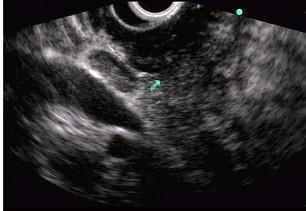

问题 男性,50岁,上腹隐痛,食欲不振3个月。1个月来出现黄疸且进行性加深,体重明显减轻,查体全身明显黄染,肝未触及,深吸气时可触到肿大胆囊底部,无触痛。化验血胆红素15mg/dl,尿检胆红素阳性图中胰腺病变可能的诊断是 ( )

选项 A、胰腺囊腺癌 B、胰腺癌 C、胰腺囊肿 D、慢性胰腺炎 E、正常

答案 B